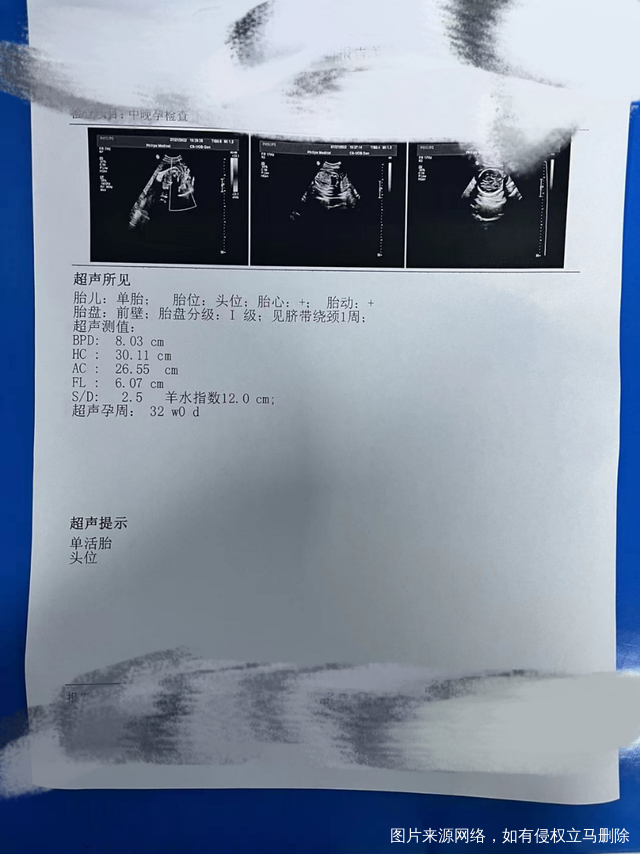

大夫你好,31加6周,上一胎孩子腿不长,这个腿可以吗?